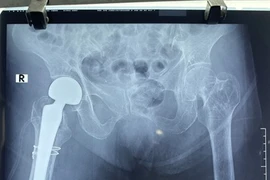

Thay khớp háng chuôi dài “cứu” gãy cổ xương đùi người già

Phẫu thuật thay khớp háng chuôi dài điều trị gãy khối máu chuyển xương đùi – giải pháp tối ưu phục hồi chức năng ở người cao tuổi.